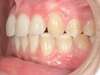

Cas N°6 : Description

Correction majeure des deux arcades dentaires liée à une mandibule rétrusive

Avant

Après